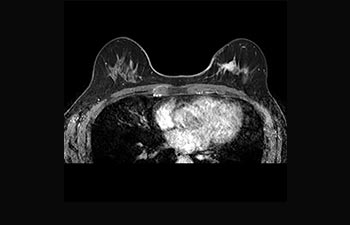

La Sra. Silvia Schiffer, directora y radióloga experta en la clínica Radiologie Schiffer, en Alemania, comparte sus experiencias con el sistema de RM Prodiva 1.5T.

Mayor fiabilidad diagnóstica en neurooncología